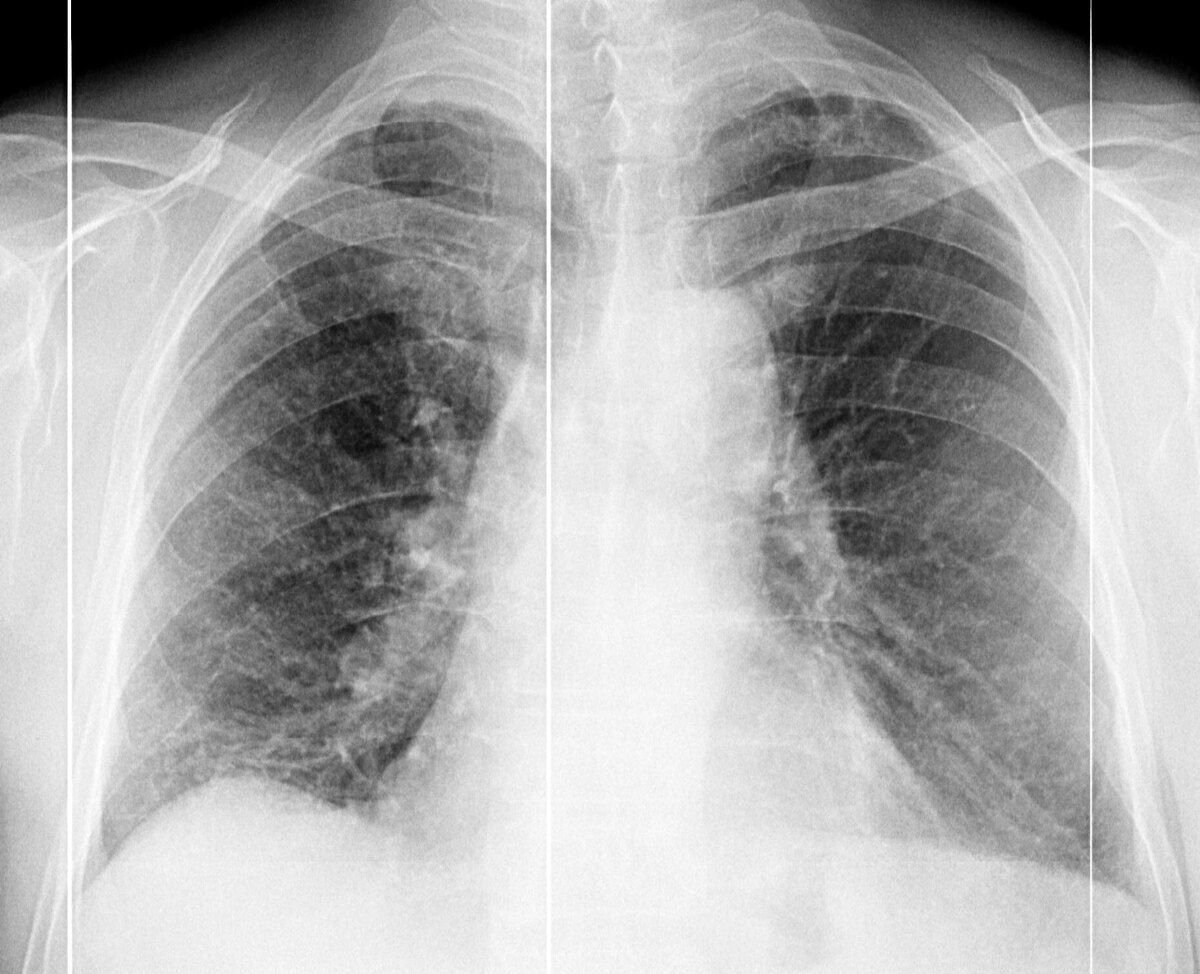

"Пятна" на флюорографии – это приговор? Разбираемся, что такое пневмосклероз и как с ним жить Вы посмотрели на снимок флюорографии и увидели загадочные "пятна"? Не спешите паниковать! Эти изменения могут оказаться признаками пневмосклероза – состояния, которое, к счастью, не всегда является "приговором". Давайте вместе разберемся, что это такое, почему появляется и что с этим делать. ▌Что такое пневмосклероз и почему он возникает? Пневмосклероз – это, по сути, рубцевание легочной ткани. Представьте себе: после раны на коже остается шрам, так и в легких, после повреждения, образуются участки с измененной структурой, состоящие из соединительной ткани. В норме наши легкие постоянно обновляются, но когда этот процесс нарушается, начинается избыточный рост соединительной ткани, что и приводит к пневмосклерозу. Факторов, способствующих этому процессу, множество: 1) Старение: К сожалению, с возрастом в легких происходят естественные изменения. После 40-50 лет, между кровеносными сосудами и ал

Вы посмотрели на снимок флюорографии и увидели загадочные "пятна"? Не спешите паниковать! Эти изменения могут оказаться признаками пневмосклероза – состояния, которое, к счастью, не всегда является "приговором". Давайте вместе разберемся, что это такое, почему появляется и что с этим делать.

Важно понимать, что наличие пневмосклероза на флюорографии – это не приговор! На ранних стадиях, он может быть не значительным, и не вызывать никаких симптомов. Однако, игнорировать этот сигнал не стоит.

Если на флюорографии выявили изменения, похожие на пневмосклероз, первое и главное – не паниковать. Вам необходимо обратиться к врачу-пульмонологу для более детального обследования. Зачастую, изменения на флюорографии могут быть связаны с небольшими воспалениями, которые со временем уходят, или артефактами снимка.

1) Рентгенография органов грудной клетки: Более детальный снимок по сравнению с флюорографией.

2) Компьютерная томография (КТ) органов грудной клетки: Самый информативный метод, позволяющий увидеть структуру легочной ткани во всех подробностях.